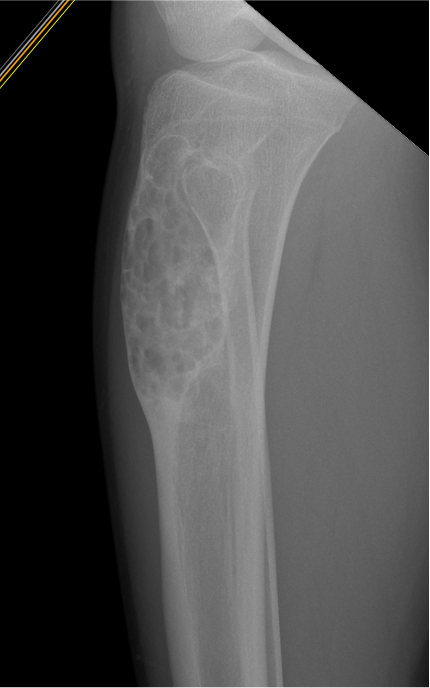

X-ray

Most common anterior cortex of tibia

Soap-bubble appearance

Eccentrically located

- well circumscribed

- slightly expansile

- cortical thickening

- little or no periosteal reaction

Khanna et al Skeletal Radiol 2008

- 24 cases of OFD / adamantinoma

- adamantinomas tend to be larger / cortical destruction / complete marrow involvement